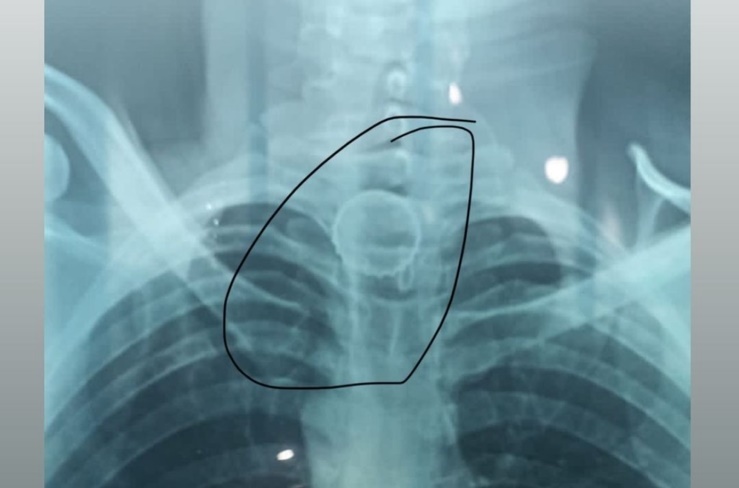

Um homem, de 35 anos, deu entrada no Hospital do Juruá por volta das 16hrs da tarde do último domingo (01), após engolir uma tampa de garrafa em Ipixuna (AM). O paciente foi encaminhado para Cruzeiro do Sul para fazer uma endoscopia e a retirada da tampa. O procedimento foi feito aproximadamente 21h do mesmo dia.